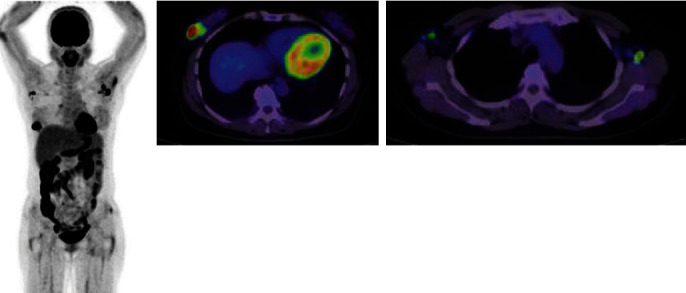

自身免疫性中性粒细胞减少症(AIN)是一种极为罕见的疾病,目前尚无有效的治疗方法。自身免疫性中性粒细胞减少症可导致围手术期感染等重大并发症。在此,我们介绍一位 56 岁的女性患者,她原计划接受乳腺癌手术。然而,她却意外地被诊断出患有 AIN。因此,手术被推迟,并开始接受内分泌治疗。治疗 7 个月后,她接受了手术。手术前注射了粒细胞集落刺激因子,但患者的中性粒细胞计数没有增加。因此,在手术中使用了左氧氟沙星。术后 1 天,患者出现发热(38.6°C)。她的手术伤口没有发红,也没有其他感染迹象。术后第二天烧退了。尽管如此,她仍服用了 5 天抗生素。患者于术后第六天出院。

Autoimmune neutropenia (AIN) is an extremely rare condition, and there is no effective treatment option for this disorder. AIN can cause major complications in patients with perioperative infection. Herein, we present a 56-year-old female patient who was scheduled for breast cancer surgery. However, she was unexpectedly diagnosed with AIN. Thus, the surgery was postponed, and endocrine therapy was started. After 7 months of treatment, the surgery was performed. Granulocyte colony-stimulating factor was administered before the surgery, but the patient's neutrophil count did not increase. Thus, levofloxacin was administered during the surgery. The patient had fever (38.6°C) 1 day after the surgery. Her surgical wound did not present with redness, and there were no other signs of infection. The fever subsided on the second day after the surgery. Nevertheless, antibiotics were administered for 5 days. The patient was discharged on the sixth day after the surgery.